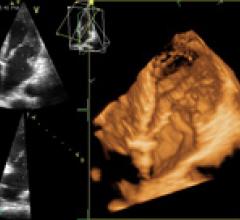

October 24, 2011 – The European Association of Echocardiography (EAE) has announced it is working together with the ...